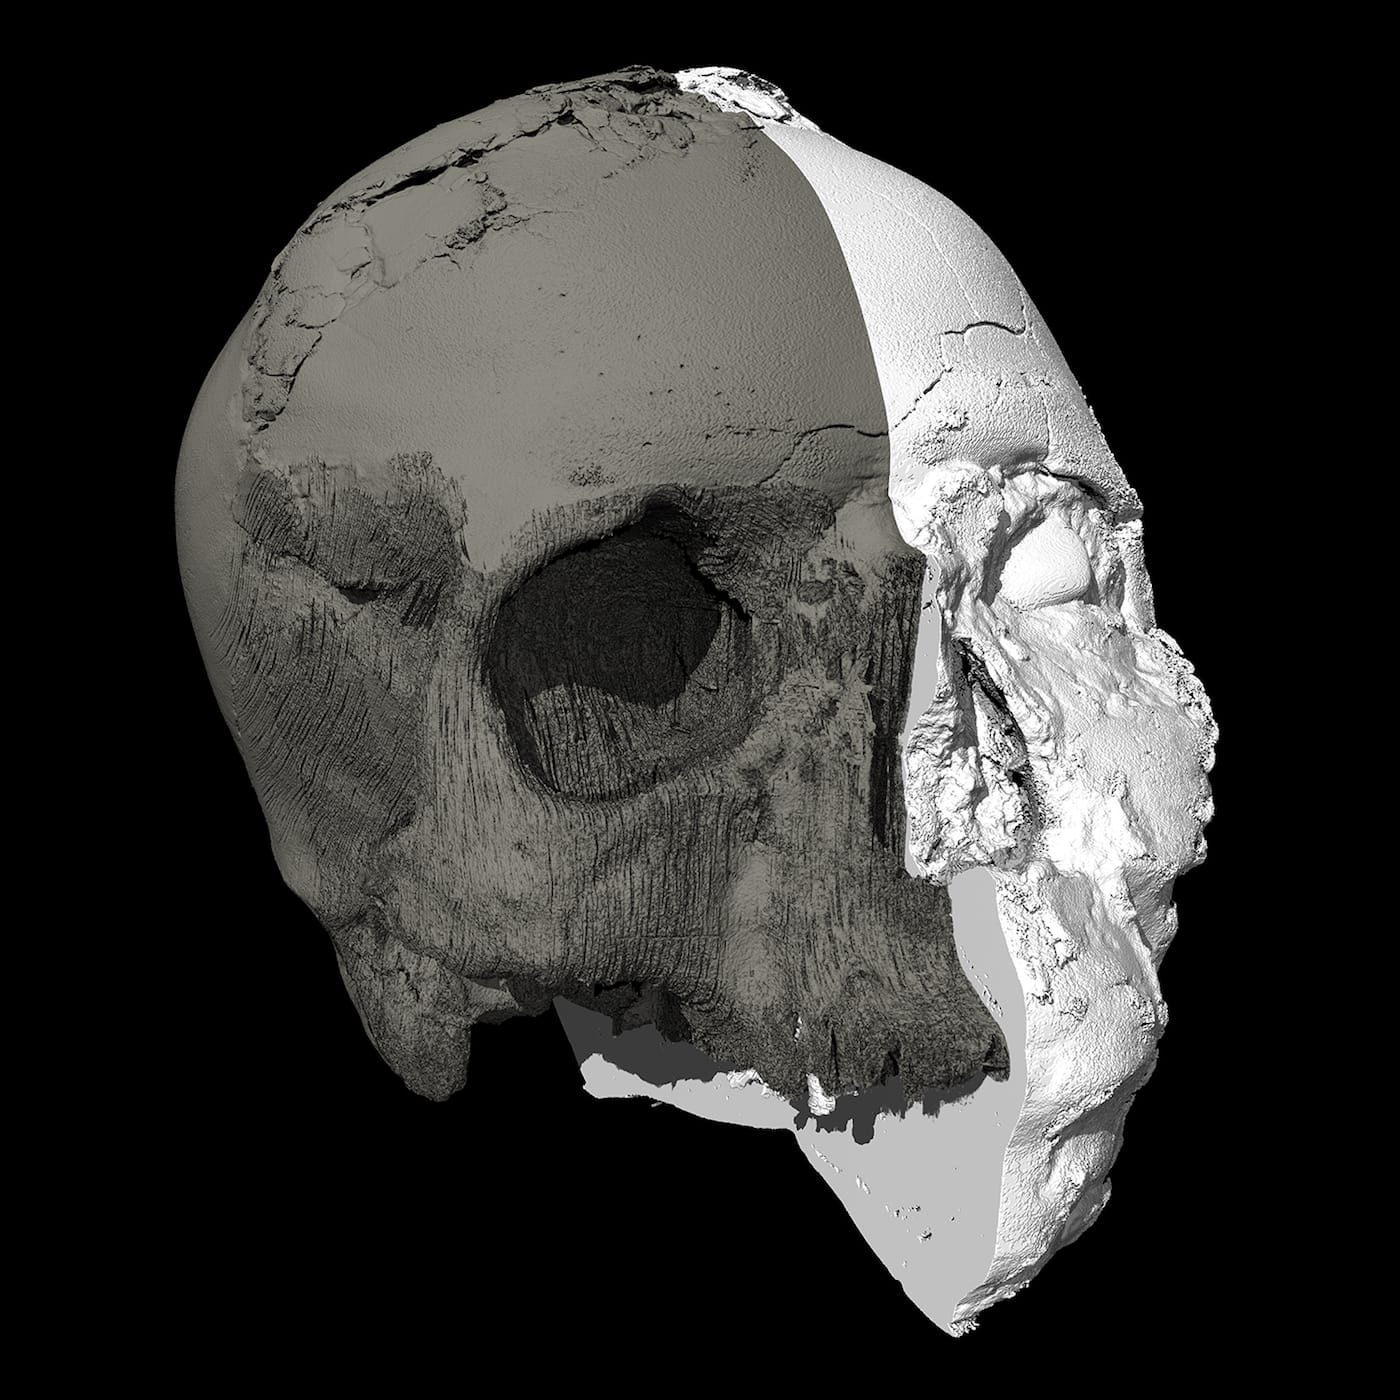

We now have an idea of what this particular individual looked like, as experts at the Natural History Museum’s Imaging and Analysis Center have used micro-CT scanning to create a 3D facial reconstruction of the Jericho Skull. The head, which is currently on display, depicts a man in at least his 40s who likely underwent ritual skull reshaping when he was younger, as suggested by the slight broadening of his head across the back.

The imaging team conducted its own sculptural process, but one, of course, aided with the latest digital technologies. Experts first digitally separated the shape of the skull bones from the overlying plaster then converted data from a micro-CT scan to create a 3D-printed model of the cranium. As the mandible was not present, the team added a lower jaw constructed based on data from other known examples of human mandibles of similar age and geographic origin. The face was then built over the skull model — this time, in a more traditional sculptural process: experts used clay and wax to build features from the bone-up, muscle by muscle, creating every anatomical detail before topping it off with a clay layer of tissue and skin. Finally, they made a mold of the head from which the displayed face was cast in Jesmonite — essentially a mixture of gypsum and acrylic resin.

Fletcher believes this is the first time anyone has attempted to reconstruct the face of someone who had their skull plastered. Although her team is unable to learn more about the mysterious man — the only possible next step, as technology stands, would be to break apart the plastered face — she hopes the project will allow museum visitors to connect with someone who lived over 9000 years ago.

“The reconstruction allows us to appreciate that this individual was a man who looked just like you or I,” Fletcher said. “Despite living a long time ago, he is the same species as people living today. The artificial re-shaping of his skull can be seen — but it is not as dramatic as you might expect. In short, he was no freak show — he looks remarkably ordinary.”